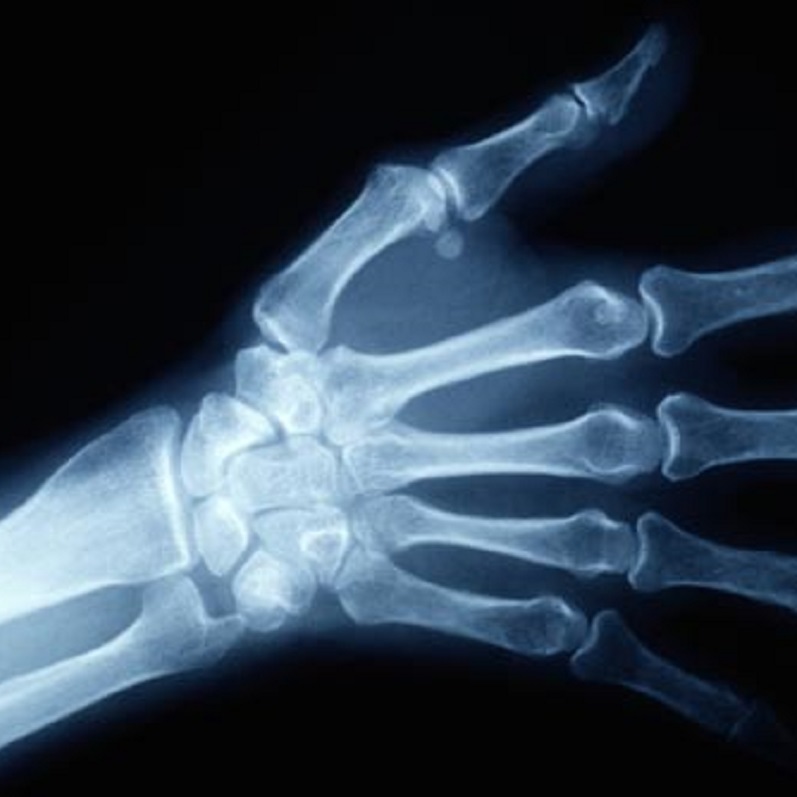

手腕生理解剖簡介

手腕由尺橈遠端、纖維軟骨、八塊腕骨及近端掌指組成,容許手腕作前屈、後伸、內收、外展、內旋及外旋動作。腕橈關節負責手腕屈伸,及尺屈橈屈的動作,而遠端尺橈關節作前臂外內旋動作。手腕腕骨包括舟骨、月骨、三角骨、豆骨、大多角骨、小多角骨、頭狀骨及鉤狀骨,並排列成遠近兩排腕骨。遠端腕骨排列緊密,活動較小;近端活動幅度較大,以協助手腕屈伸動作。